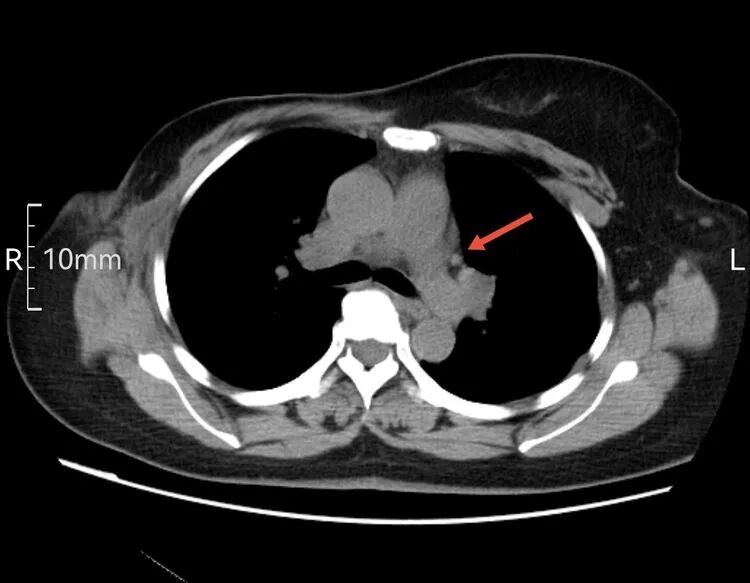

以下是患者的CT表现:

为什么建立双输液通道输液港 偶遇“双上腔静脉”_https://www.jmylbn.com_新闻资讯_第4张

箭头所指为左侧“上腔静脉”走行  虽然过程不寻常,但在血管造影辅助下显示其“真容”后,导管经左侧颈内静脉,避开变异的“左上腔静脉”并通过左侧头臂干,导管头端留置在正常的上腔静脉内。成功给予患者植入左侧胸壁港。